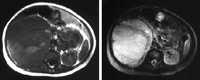

Wilms' tumour

Wilms' tumour: MRI findings

UHRAD.com; used with permission